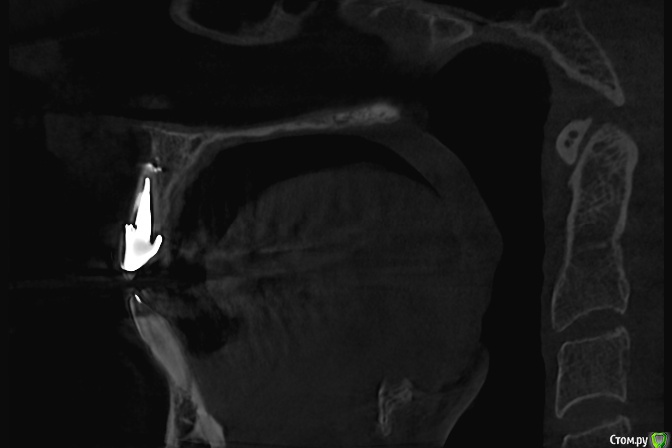

Zelenoglazka Опубликовано 13 мая, 2017 Автор Поделиться Опубликовано 13 мая, 2017 Здравствуйте! В общем продолжение следует...Терапевт, у которого лечила соседний с коронкой зуб, проконсультировался по КТ с их хирургом, оба решили, что кончик канала не запломбирован и требуется резекция с запечатыванием среза специальным цементом (практически дословно цитирую). Я спросила у терапевта про ретроградное пломбирование (хотя сама до конца не понимаю в чем оно заключается), что нет смысла, туда не подлезешь и вообще он не видели, чтобы так делали...Я решила сходить в другую клинику - там хирург, посмотрев внимательно КТ и рентген, сказал, что видит след пломбировоного материала в канале и что резекция мне не нужна и даже может быть опасна расколом корня. А затем увидел на КТ и показал мне признаки возможной трещины корня - вышедший сквозь стенку корня цемент, на которую устанавливается вкладка Ссылка на комментарий

Zelenoglazka Опубликовано 13 мая, 2017 Автор Поделиться Опубликовано 13 мая, 2017 Постаралась найти и сохранить срезы, которые он мне показывал Ссылка на комментарий